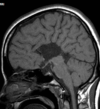

Q

A

Esclerose mesial temporal

Observe a perda de volume, que indica atrofia e causa aumento secundário do corno temporal do ventrículo lateral.

O sinal alto no hipocampo reflete a gliose.

Atrofia hipocampal e hipersinal T2. Cerca de 10% dos casos são bilaterais (dificulta o diagnóstico). A etiologia é desconhecida, mas há uma relação entre STM e convulsões febris prolongadas no início da vida A esclerose mesial temporal pode ocorrer em associação com outras patologias, principalmente displasia cortical focal (dual pathology).

203